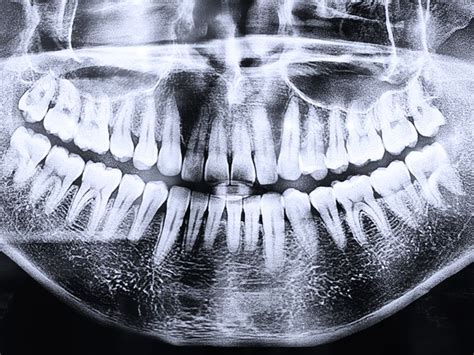

¿Qué es la Ortopantomografía Dental y Para Qué Sirve?

La ortopantomografía dental es una radiografía panorámica que permite obtener una imagen en dos dimensiones de toda la estructura bucal: mandíbula, dientes, encías y huesos maxilares. Es una herramienta diagnóstica fundamental en odontología moderna, utilizada en múltiples tratamientos dentales gracias a su precisión y rapidez.